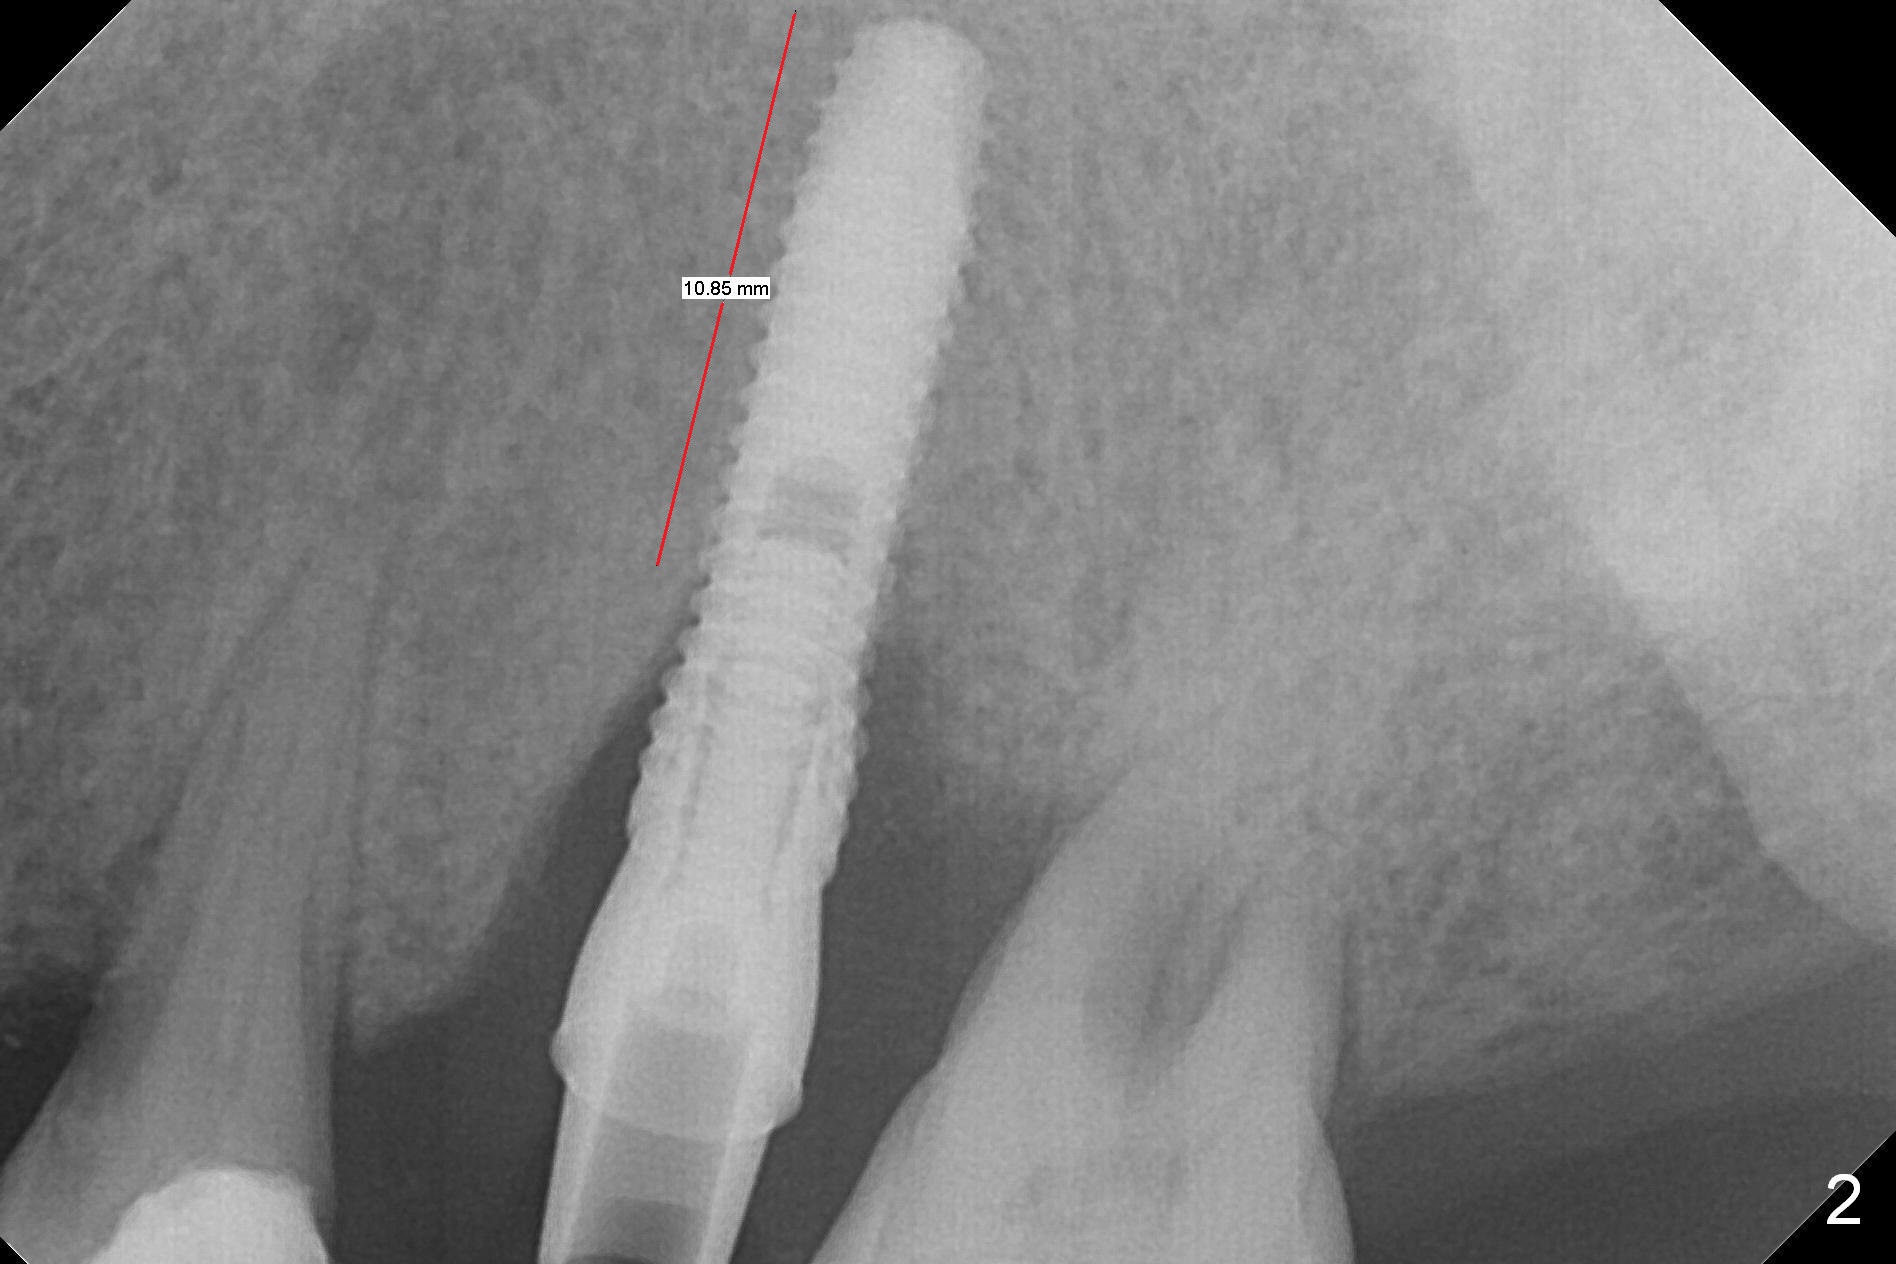

Initial osteotomy depth is 18 mm (Fig.1 green line) with 9 mm in the native bone (red line).  The bone density feels to be low.  There is at least 2 more mm bone apically (pink line).  The depth is increased by 2 mm so that when a 3.8x15 mm implant is placed, there is 10-11 mm implant/bone contact (Fig.2 red line).  There is large bony defect (Fig.3 *), which is bone grafted (Fig.4 *).  Finally a longer abutment is placed (4.5x5.5(5) in Fig.4 vs. 4.5x4(5) in Fig.2,3).  The 5 mm cuff does not look too long buccally (Fig.5) or palatally (Fig.6).   To prevent postop buccal gingival overgrowth (2), the buccal margin of an immediate provisional is subgingival (Fig.7-9 *).  Bone density between #13 and 14 appears to increase 3 months postop (Fig.10).  The implant seems to be equi-crestal (Fig.11 ^).  There seems to be more bone growth (i.e., decreasing gap) 6 months postop (Fig.12).  Impression is taken.  A crown is delivered nearly 7 months postop (08/07/2017).   While there is minimal bone loss at #13 and 15 three years and 4 months post cementation, the tooth #14 and 18 are mobile (Fig.13,14).